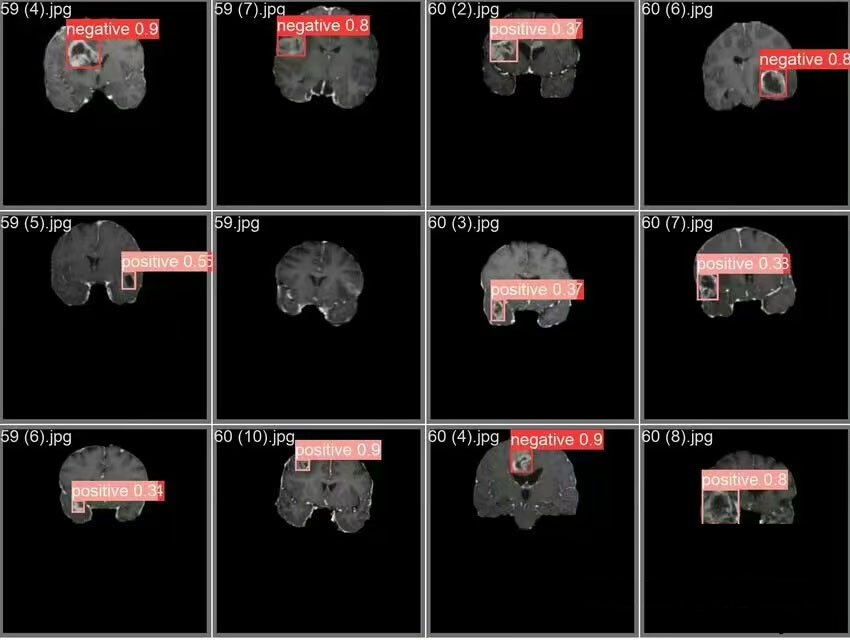

包含對(duì)應(yīng)的txt標(biāo)簽,檢測(cè)效果如圖

0和1是分別對(duì)應(yīng)negative和 positive